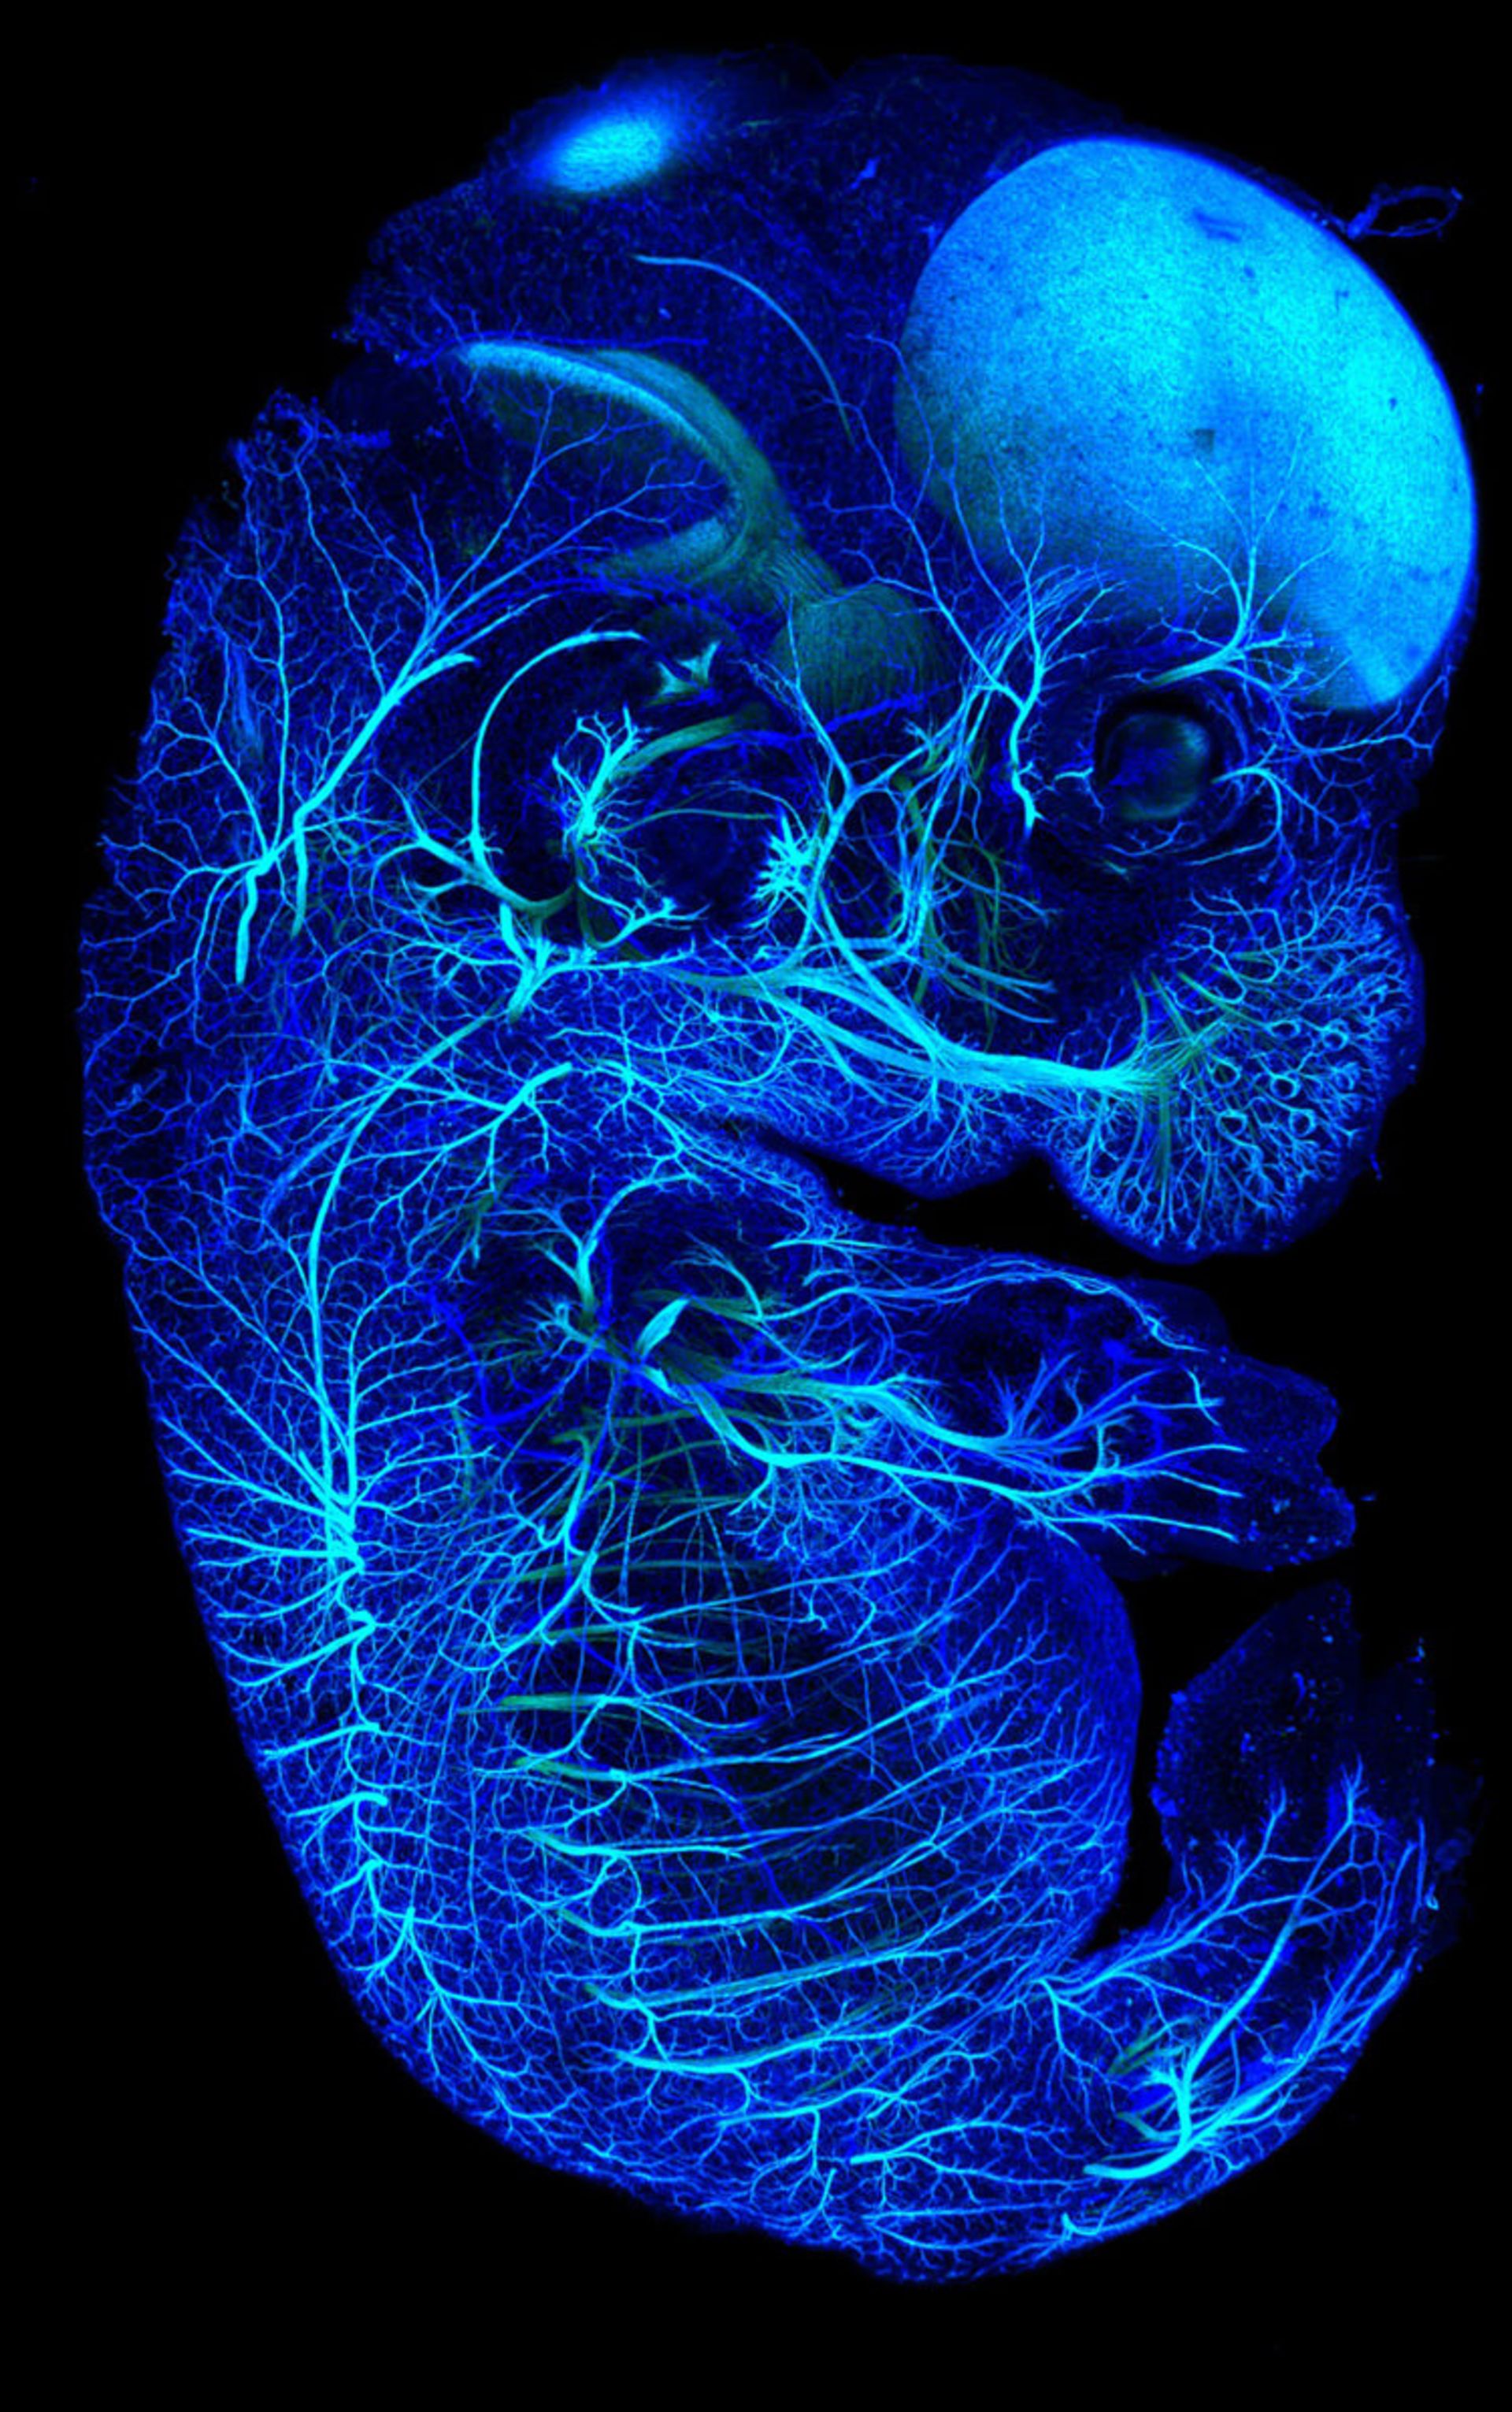

اعصاب (بهرنگ آبی روشن) و رگهای خونی (بهرنگ آبی تیره) در جنین ۱۳.۵ روزهی موش؛ بزرگنمایی ۱۰ برابری

ناتان برنز (Nathan Burns) از آمریکا